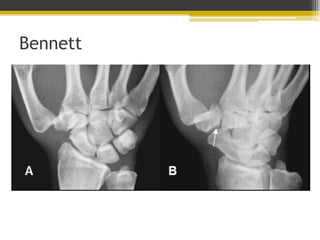

Fractura de Bennett

• Fractura intraarticular con dos

fragmentos en la base del

metacarpiano del pulgar.

• Articulación trapeciometacarpiana

Bennett